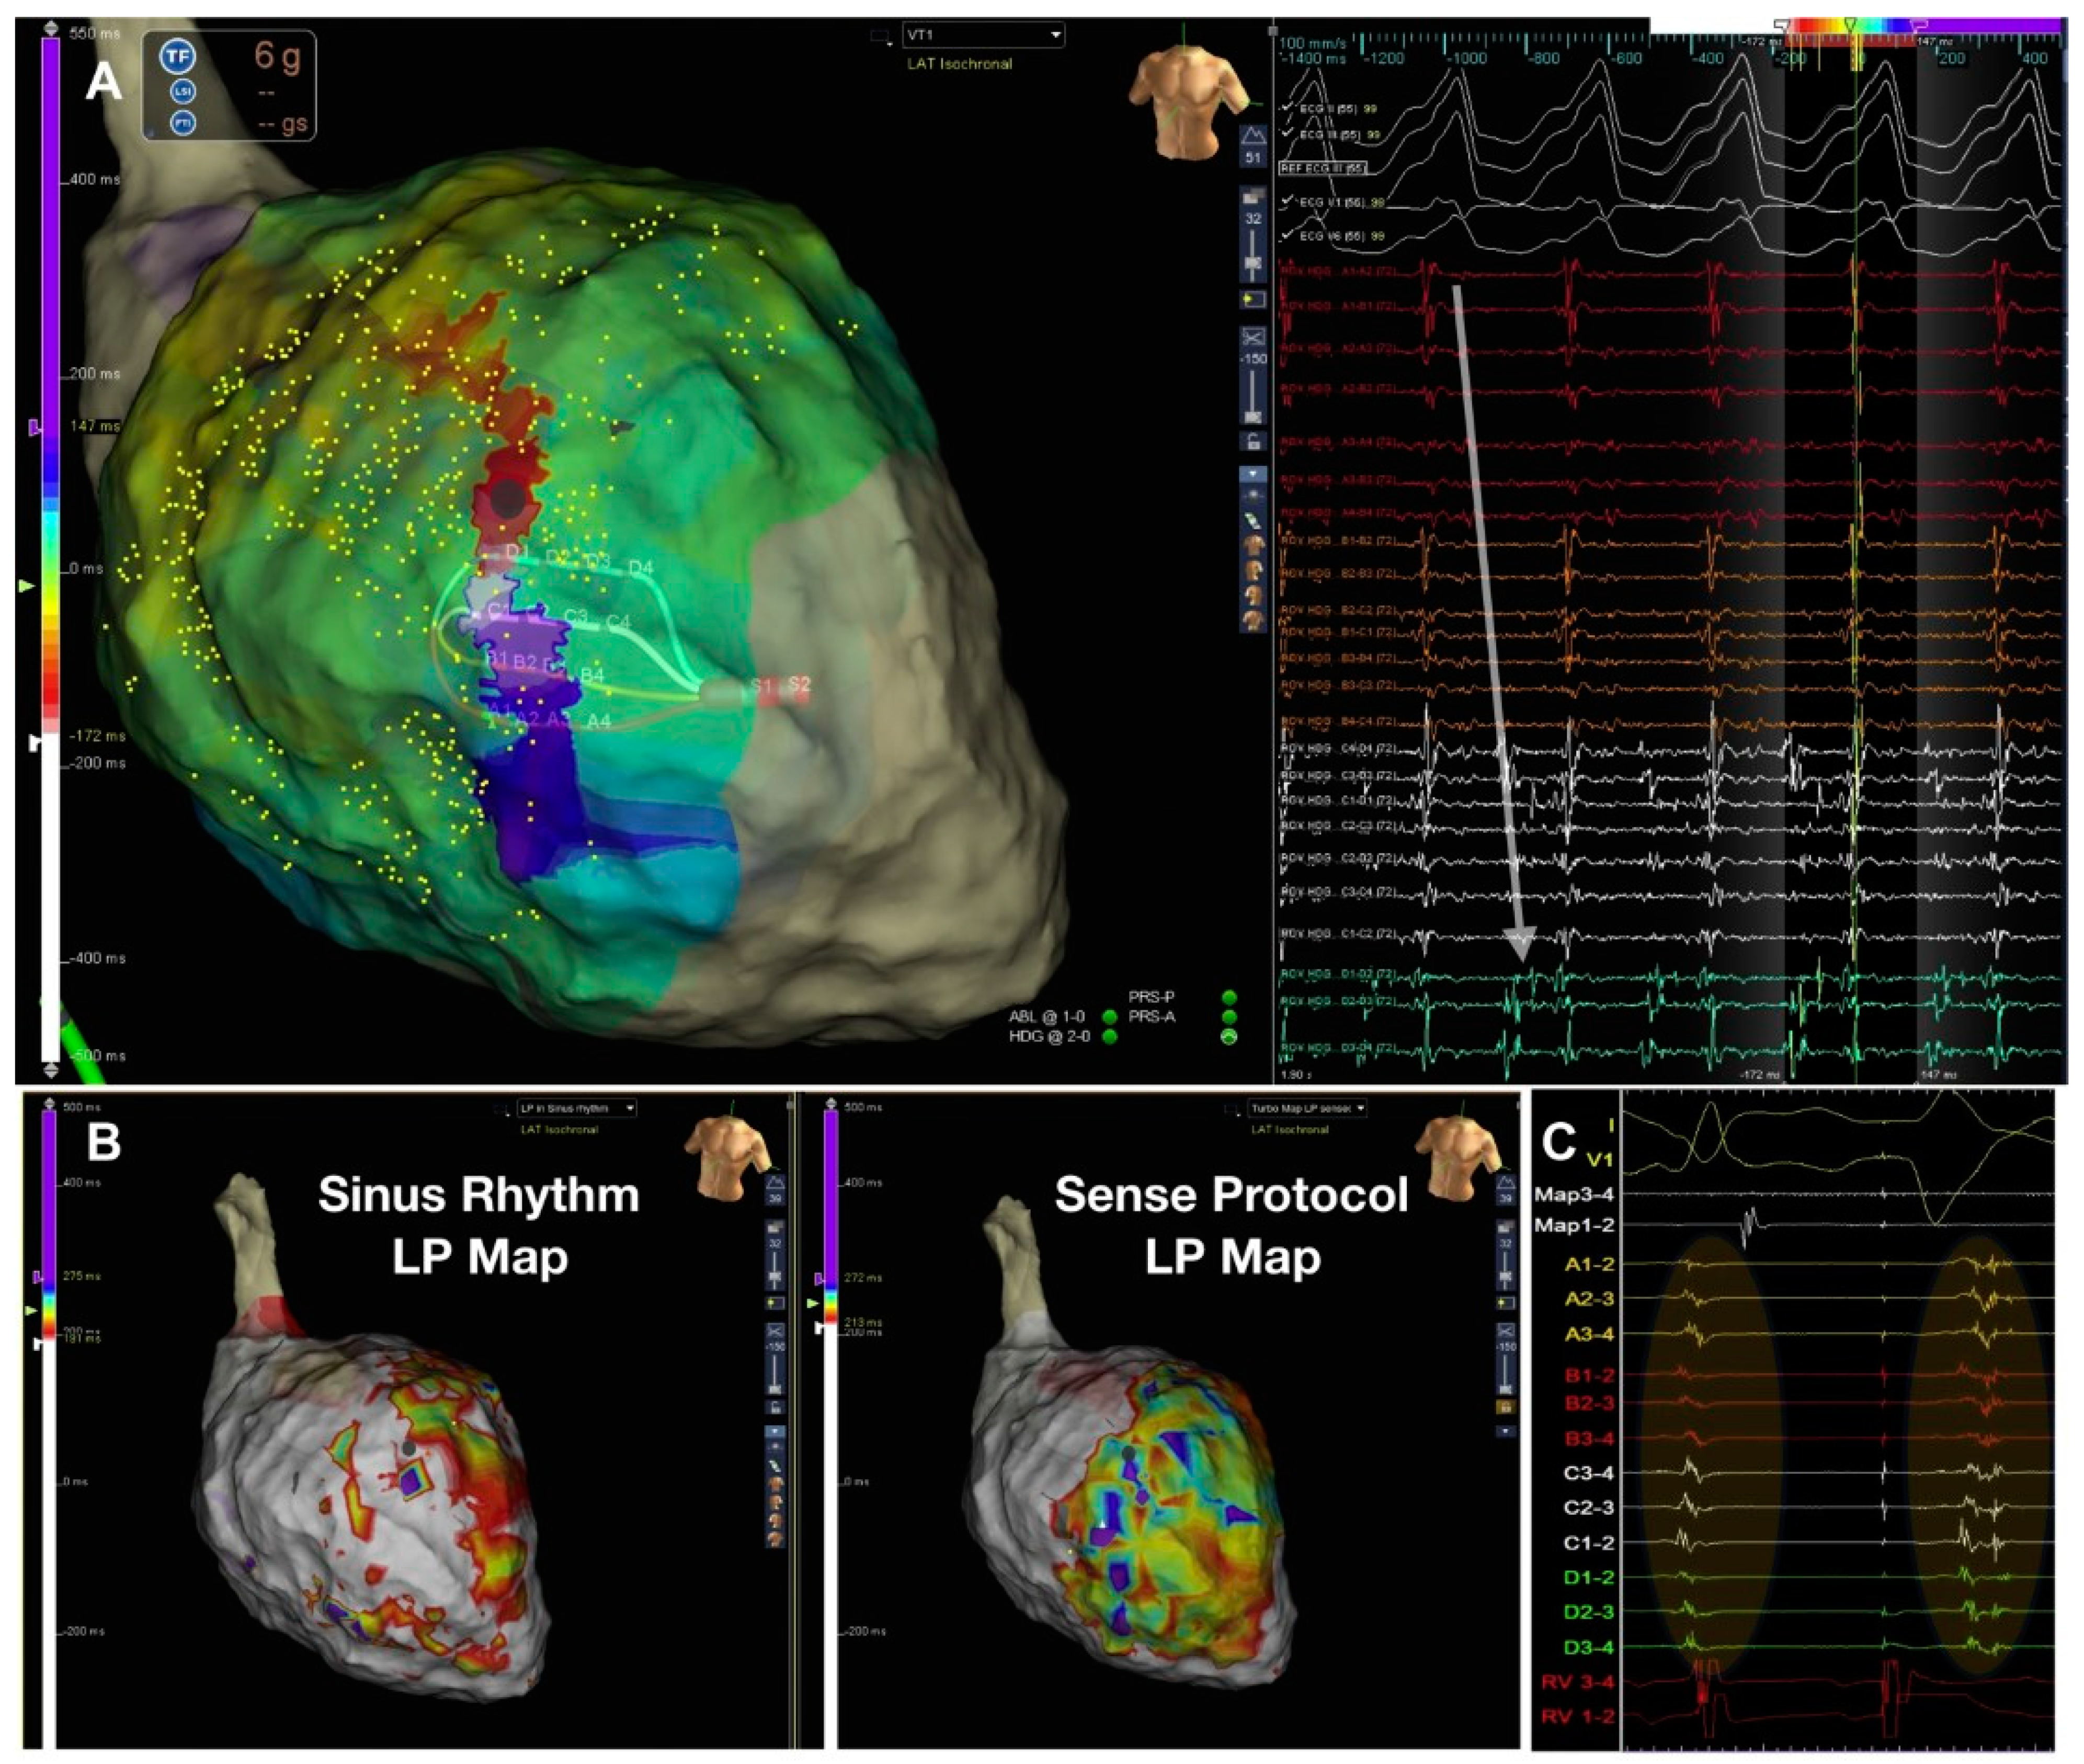

3.7. Isochronal Late Activation Mapping (ILAM)

- Aziz, Z.; Shatz, D.; Raiman, M.; Upadhyay, G.A.; Beaser, A.D.; Besser, S.A.; Shatz, N.A.; Fu, Z.; Jiang, R.; Nishimura, T.; et al. Targeted Ablation of Ventricular Tachycardia Guided by Wavefront Discontinuities during Sinus Rhythm: A New Functional Substrate Mapping Strategy. Circulation 2019, 140, 1383–1397. [Google Scholar]